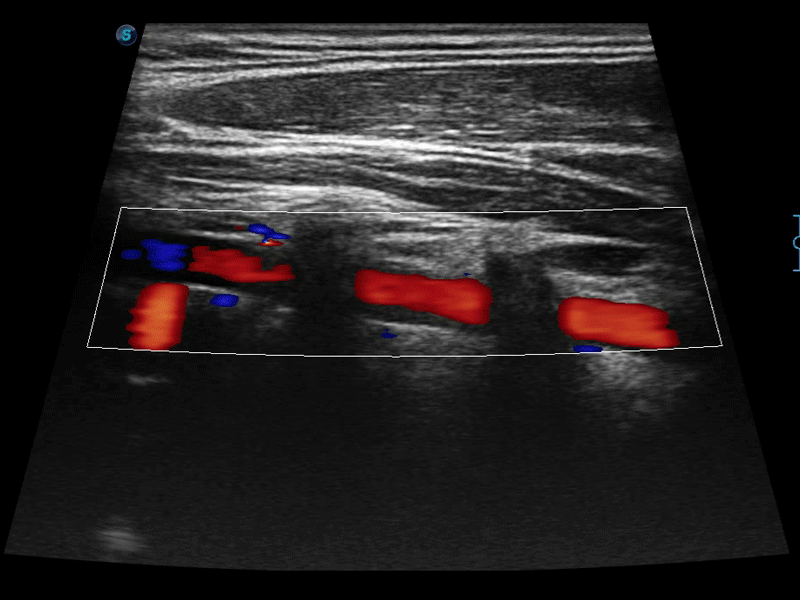

凸陣、線陣和相控陣探頭進行實時掃描時,開啟擴展成像模式,可以擴展超聲圖像視野,以便更完整地查看大的病灶或組織器官的解剖結構。

通過色彩血流和實時寬景相結合,可觀察到完整的靜脈或動脈的血流,方便醫(yī)生檢查。實時掃查過程中,如有任何操作失誤也可以很容易地進行回掃擦除,而不會中斷掃查。